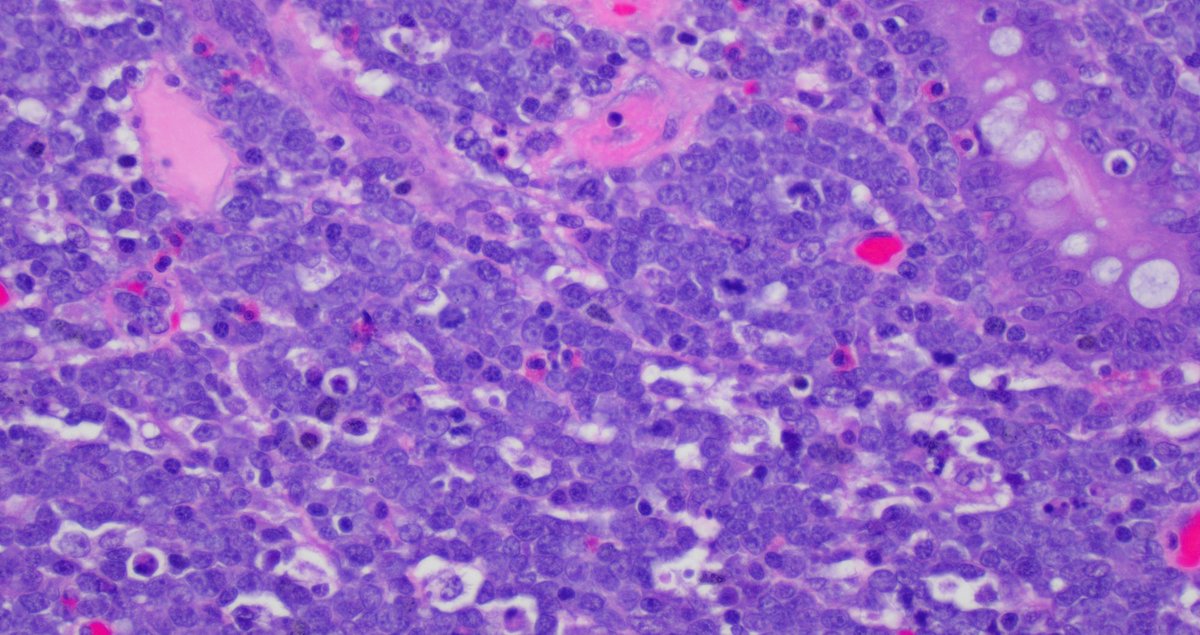

BMB 41 yo male. All these cells are positive for CD3, CD5, CD2, CD7. In the pics you can see the CD4 and CD8. What is your diagnosis? What other stains would you like to see?

Tiger_heme's tweet image. BMB 41 yo male. All these cells are positive for CD3, CD5, CD2, CD7. In the pics you can see the CD4 and CD8. What is your diagnosis? What other stains would you like to see?